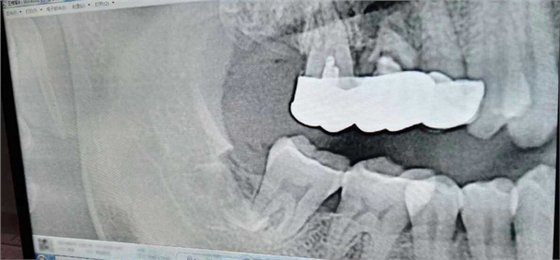

病例:患者男性47歲

右下8骨埋伏并且黏連;從根分叉處通過;有彈性;術(shù)中看到神經(jīng)束

實(shí)在找不到;近中牙冠沒去干凈

像這種不切除的牙冠,以后吸收的可能性不是很大,但有排除的可能性,自己自行排出,要是牙根的話吸收的可能性比較大

像這種沒有癥狀的殘留牙體組織不用去除可以吧